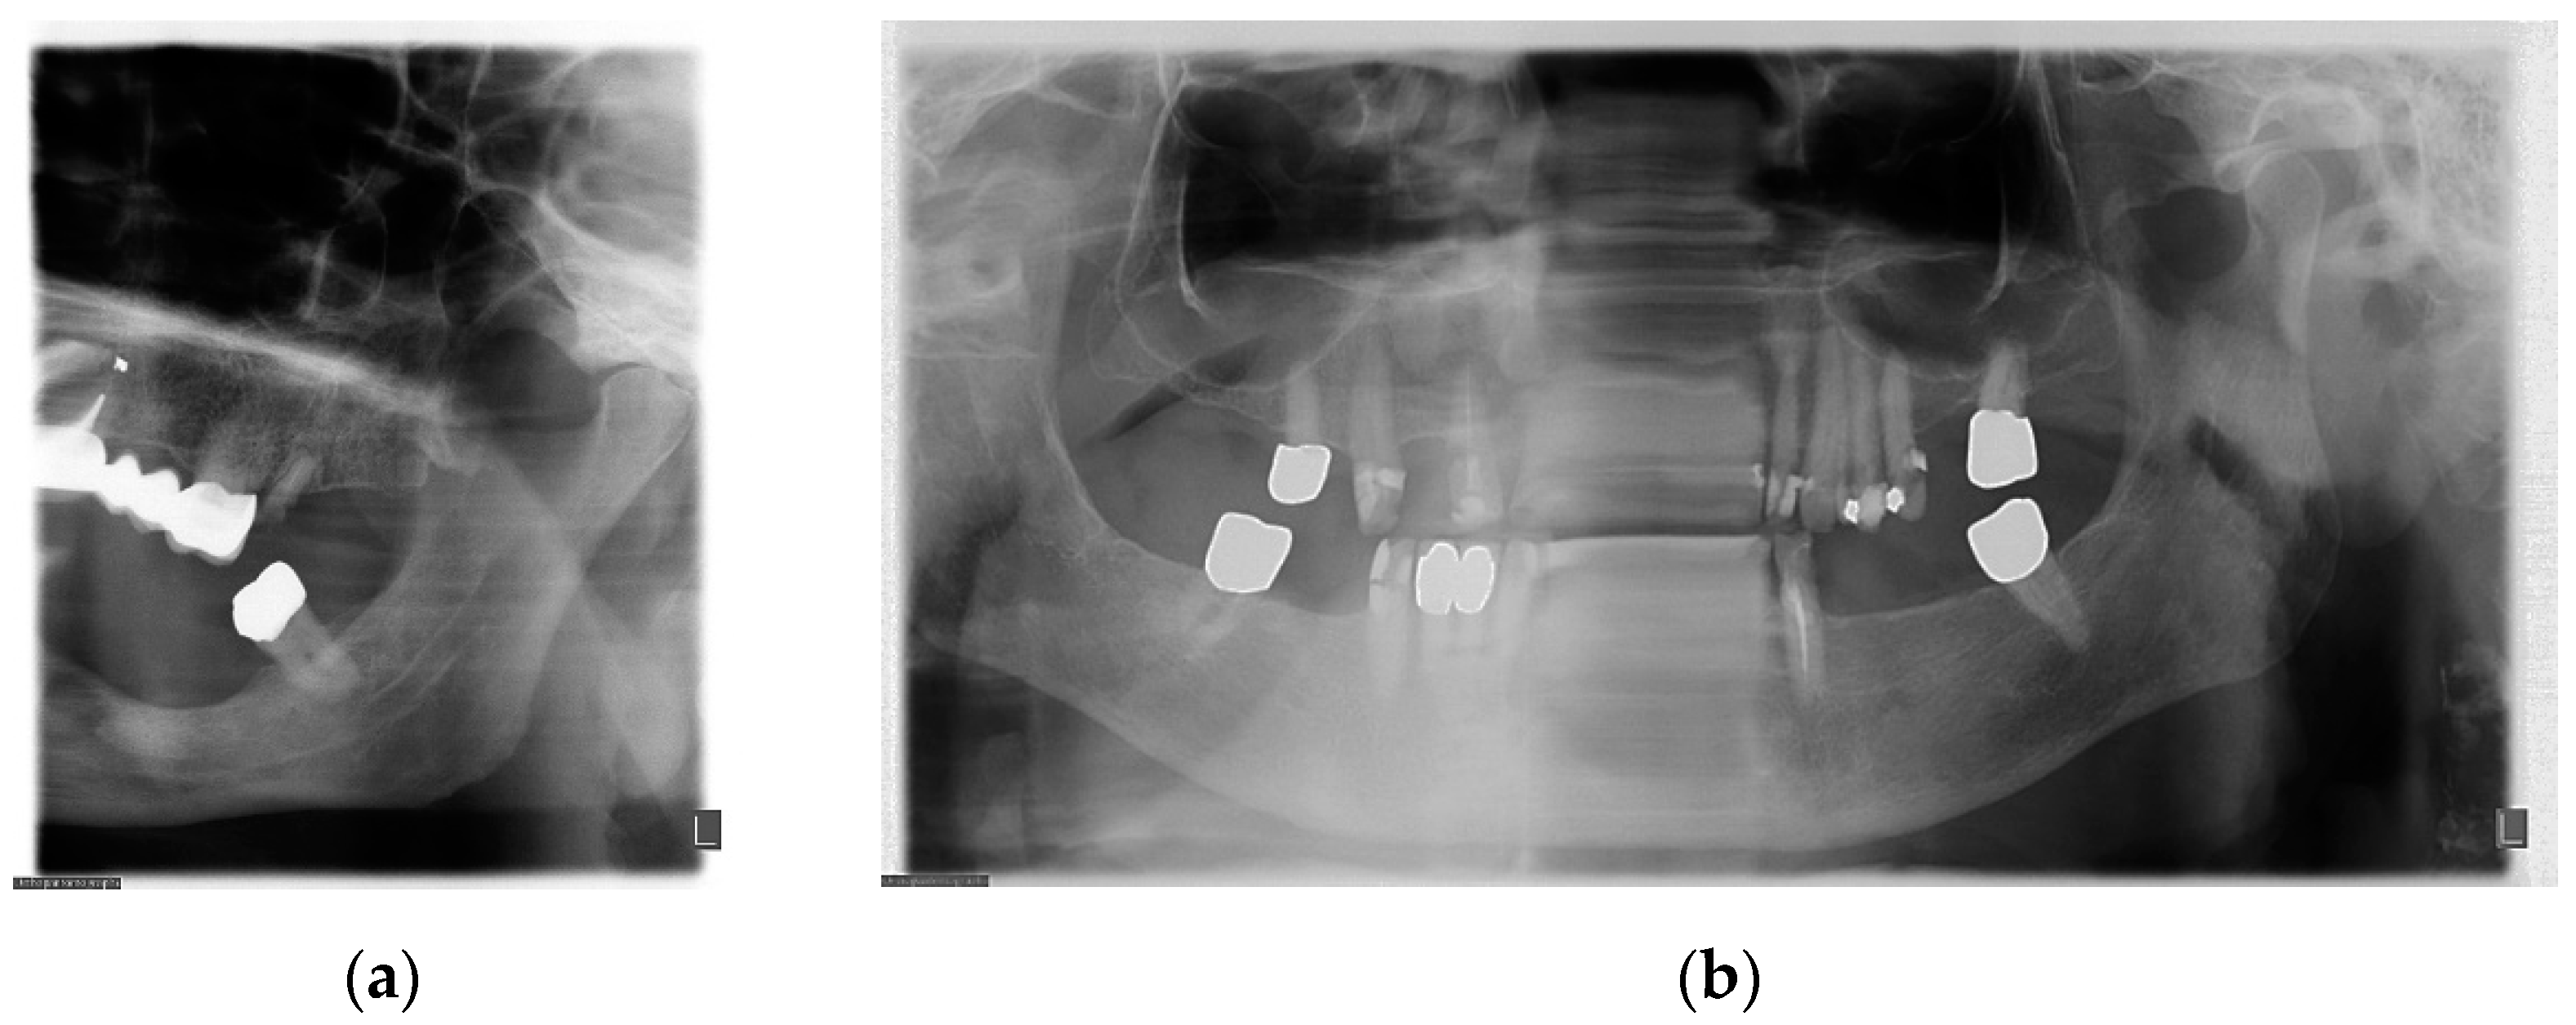

6. Evaluation of PAN Examination

7. Metal and Motion Artefacts